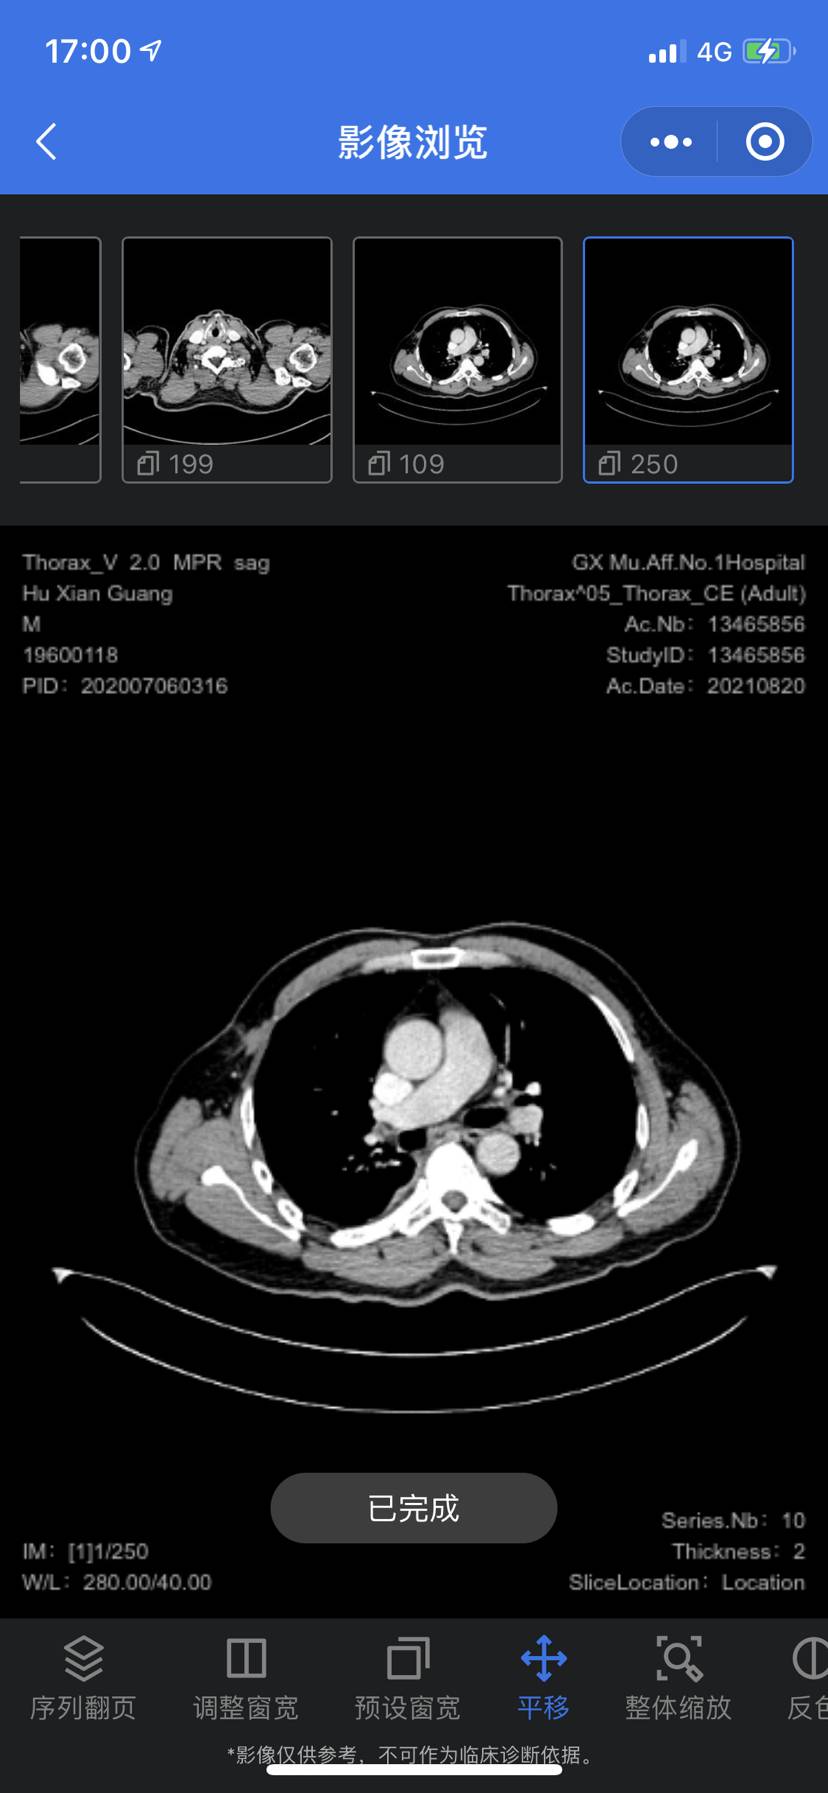

术后大半年,肺内转移?还是新发

术后化疗4次,后面一直空窗,定期复查发现可能转移瘤,请问下一步该怎么做?有人回答下吗。正在医院挂号,都没有号,都在等,心好累,去年11月份手术,目前患者身体无任何症状

大小也不小了,建议有条件的话做下穿刺,取组织做病理,确定是转移灶还是原发灶,如果确实是转移灶,可以继续启用化疗联合免疫,原发灶就要另做打算